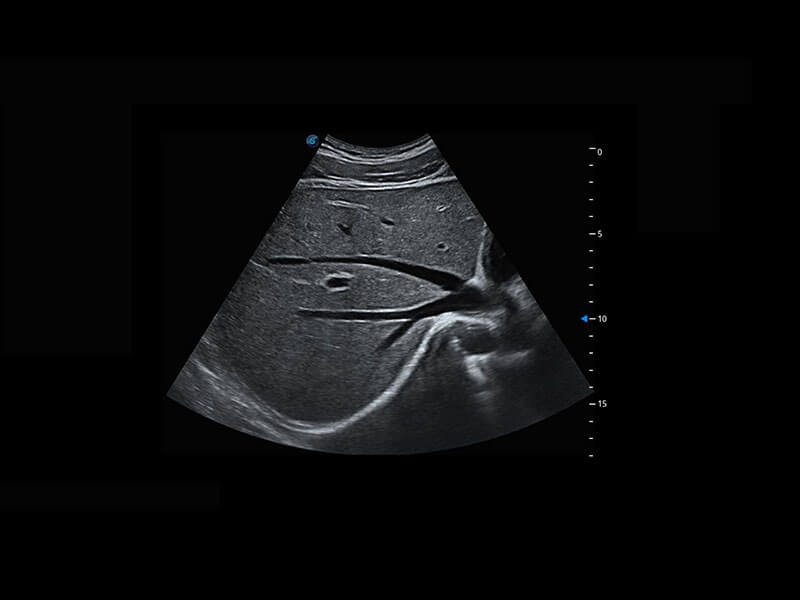

生殖健康

P60优异的图像质量搭载专科探头,在妇科基础疾病的诊断、卵泡生长的监测、输卵管通畅情况的判别等方面为您提供生殖应用方案。

• 腔内妇科-宫腔分离